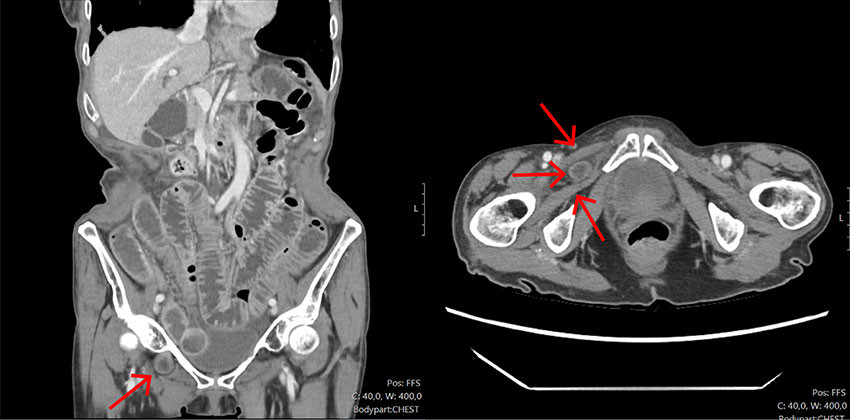

On day four, the woman's condition deteriorated, presenting with tachycardia (heart rate of 119 bpm), a respiratory rate of 28 breaths per minute (normal range: 12–16), and a fever of 38.1°C. Her CRP level also increased from 50 to 250 mg/L. Piperacillin-tazobactam was initiated intravenously at a weight-adjusted dose of 2 g x 4, and she was referred for a CT scan of the chest/abdomen/pelvis due to suspected sepsis from an abdominal focus. The CT scan revealed an incarcerated loop of small bowel protruding through the right obturator canal and pre-obstructive small bowel dilation, consistent with an acute, irreducible obturator hernia (Figures 1a and 1b). The on-call surgeon was promptly consulted, and the patient was scheduled for emergency surgery.